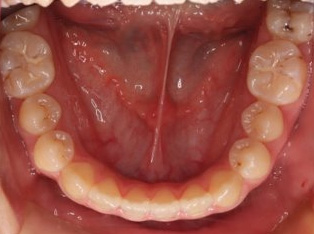

乱ぐい歯、でこぼこがとても酷い状態になります。歯が前後的に重なってしまっている、八重歯になっているなどがこのジャンルに入ります。

顎の大きさと歯の大きさのギャップが大きく、時には歯を抜かないと矯正治療ができない場合もあります。当院では治療期間が長くなるが抜かない治療方針など、一つの治療プランだけでなく、さまざまな可能性の治療方針を説明させて頂くよう心掛けております。こういった考え方はインフォームド・チョイスと言われ近年大切にされている考え方と言われております。

治療前

治療終了前